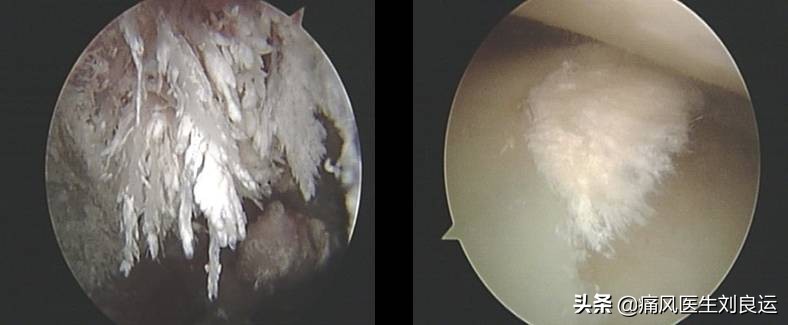

针刀镜下尿酸盐结晶

痛风发作主要是由于体内的尿酸升高导致析出的尿酸盐结晶在关节处沉积造成的炎症反应。临床上,也把有没有尿酸盐结晶作为判断痛风的关键。就是说,引起疼痛的不是尿酸高这么简单,而是尿酸盐结晶沉积后对关节造成的侵蚀。尿酸盐结晶在关节及其周围组织中的沉积是痛风发作的始动因素,不但引发天然免疫反应,而且可对局部组织造成直接损伤,加重局部炎症。

- 1.针刀镜快速降尿酸:治疗痛风需要以各种途径加速体内的尿酸结晶排出。单纯的药物治疗能起到溶解部分尿酸盐结晶并协助排出,但沉积在关节中的尿酸结晶单靠药物难以完全清除。就痛风性关节炎而言,减少尿酸生成、促进其排泄是治疗的根本,针刀镜通过关节内滑膜、软骨表面钝剥以及关节腔内的充分灌洗,可以清除关节滑液及滑膜、软骨表面的致炎因子、纤维素、纤维连接蛋白、沉积的免疫复合物等,在消除针刀镜所治疗的关节局部炎症的同时,减少关节局部免疫原性复合物对机体免疫应答反应,调控自身免疫紊乱,遏制风湿病全身病情的进展。同时通过解除关节内外的组织粘连、削剥增生的滑膜,清除血管翳或尿酸盐结晶,可以迅速、明显的改善关节活动度,尤其是膝关节,双侧膝关节腔内的关节滑膜,可以占到全身关节滑膜的50%以上,双膝关节腔的灌洗、滑膜的削剥以及药物的灌注,针对缓解全身的风湿病病情大有益处。对局部关节进行针刀镜诊治,一则进一步明确病情及诊断,二则通过关节腔冲洗、部分痛风石刮除及关节松解能够迅速缓解关节红肿热痛的炎症反应、改善关节功能,序贯以经筋刀等治疗,能够疏通经络,进一步改善症状。

针刀镜下痛风治疗